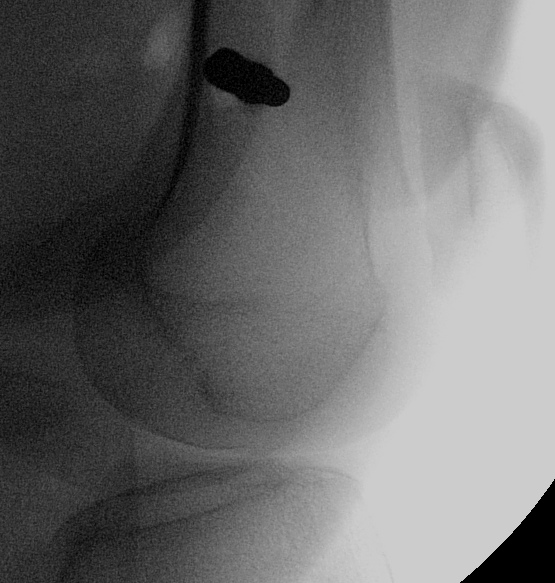

Posterior Column & Wall Fracture

Position

- IDC, radiolucent table, IV Abx

- lateral position but patient rolled excessively over

- patient 45o up from table, exposes posterior

- top leg hip flexed, knee flexed

- bottom leg extended

- blankets under top leg

- lateral support in front of top knee to prevent too much hip flexion

- prevents excessive tension on sciatic nerve

Standard posterior approach

- divide fascia lata

- find and protect sciatic nerve at all times

- do so by keeping hip extended and knee flexed

- expose short external rotators, divide 1cm from insertion to preserve blood supply

- usually must divide some of G. max

- elevate G medius from ilium

- steinmann pin in ilium for exposure

- expose ischial tuberosity by elevating biceps femoris, again protecting sciatic nerve at all time

- steinmann pin in ischium

Reduction can be aided but applying femoral distracter

- between ilial and ischial pins